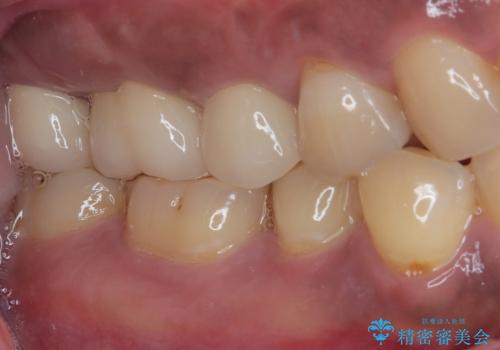

不快感の強い奥歯 オールセラミッククラウンでのむし歯治療

- とにかく奥歯に不快感を感じるとのことで来院された患者様です。

神経近くにまで及んでいる大きなむし歯や、歯肉の中深く、骨の近くにまでむし歯が進行している歯など、問題の多い状態でした。

神経を温存するための処置や、歯肉深くにまで及んだむし歯を改善するための歯周外科処置などを行っていき、オールセラミッククラウンにて補綴治療を行うこととしました。

術前の診断では神経が温存できるか否か、際どい状況でしたが、治療開始前の海外への帰省の際に自発痛(何もしなくてもズキズキ痛む)の症状が出てしまい、根管治療が必要となってしまいました。